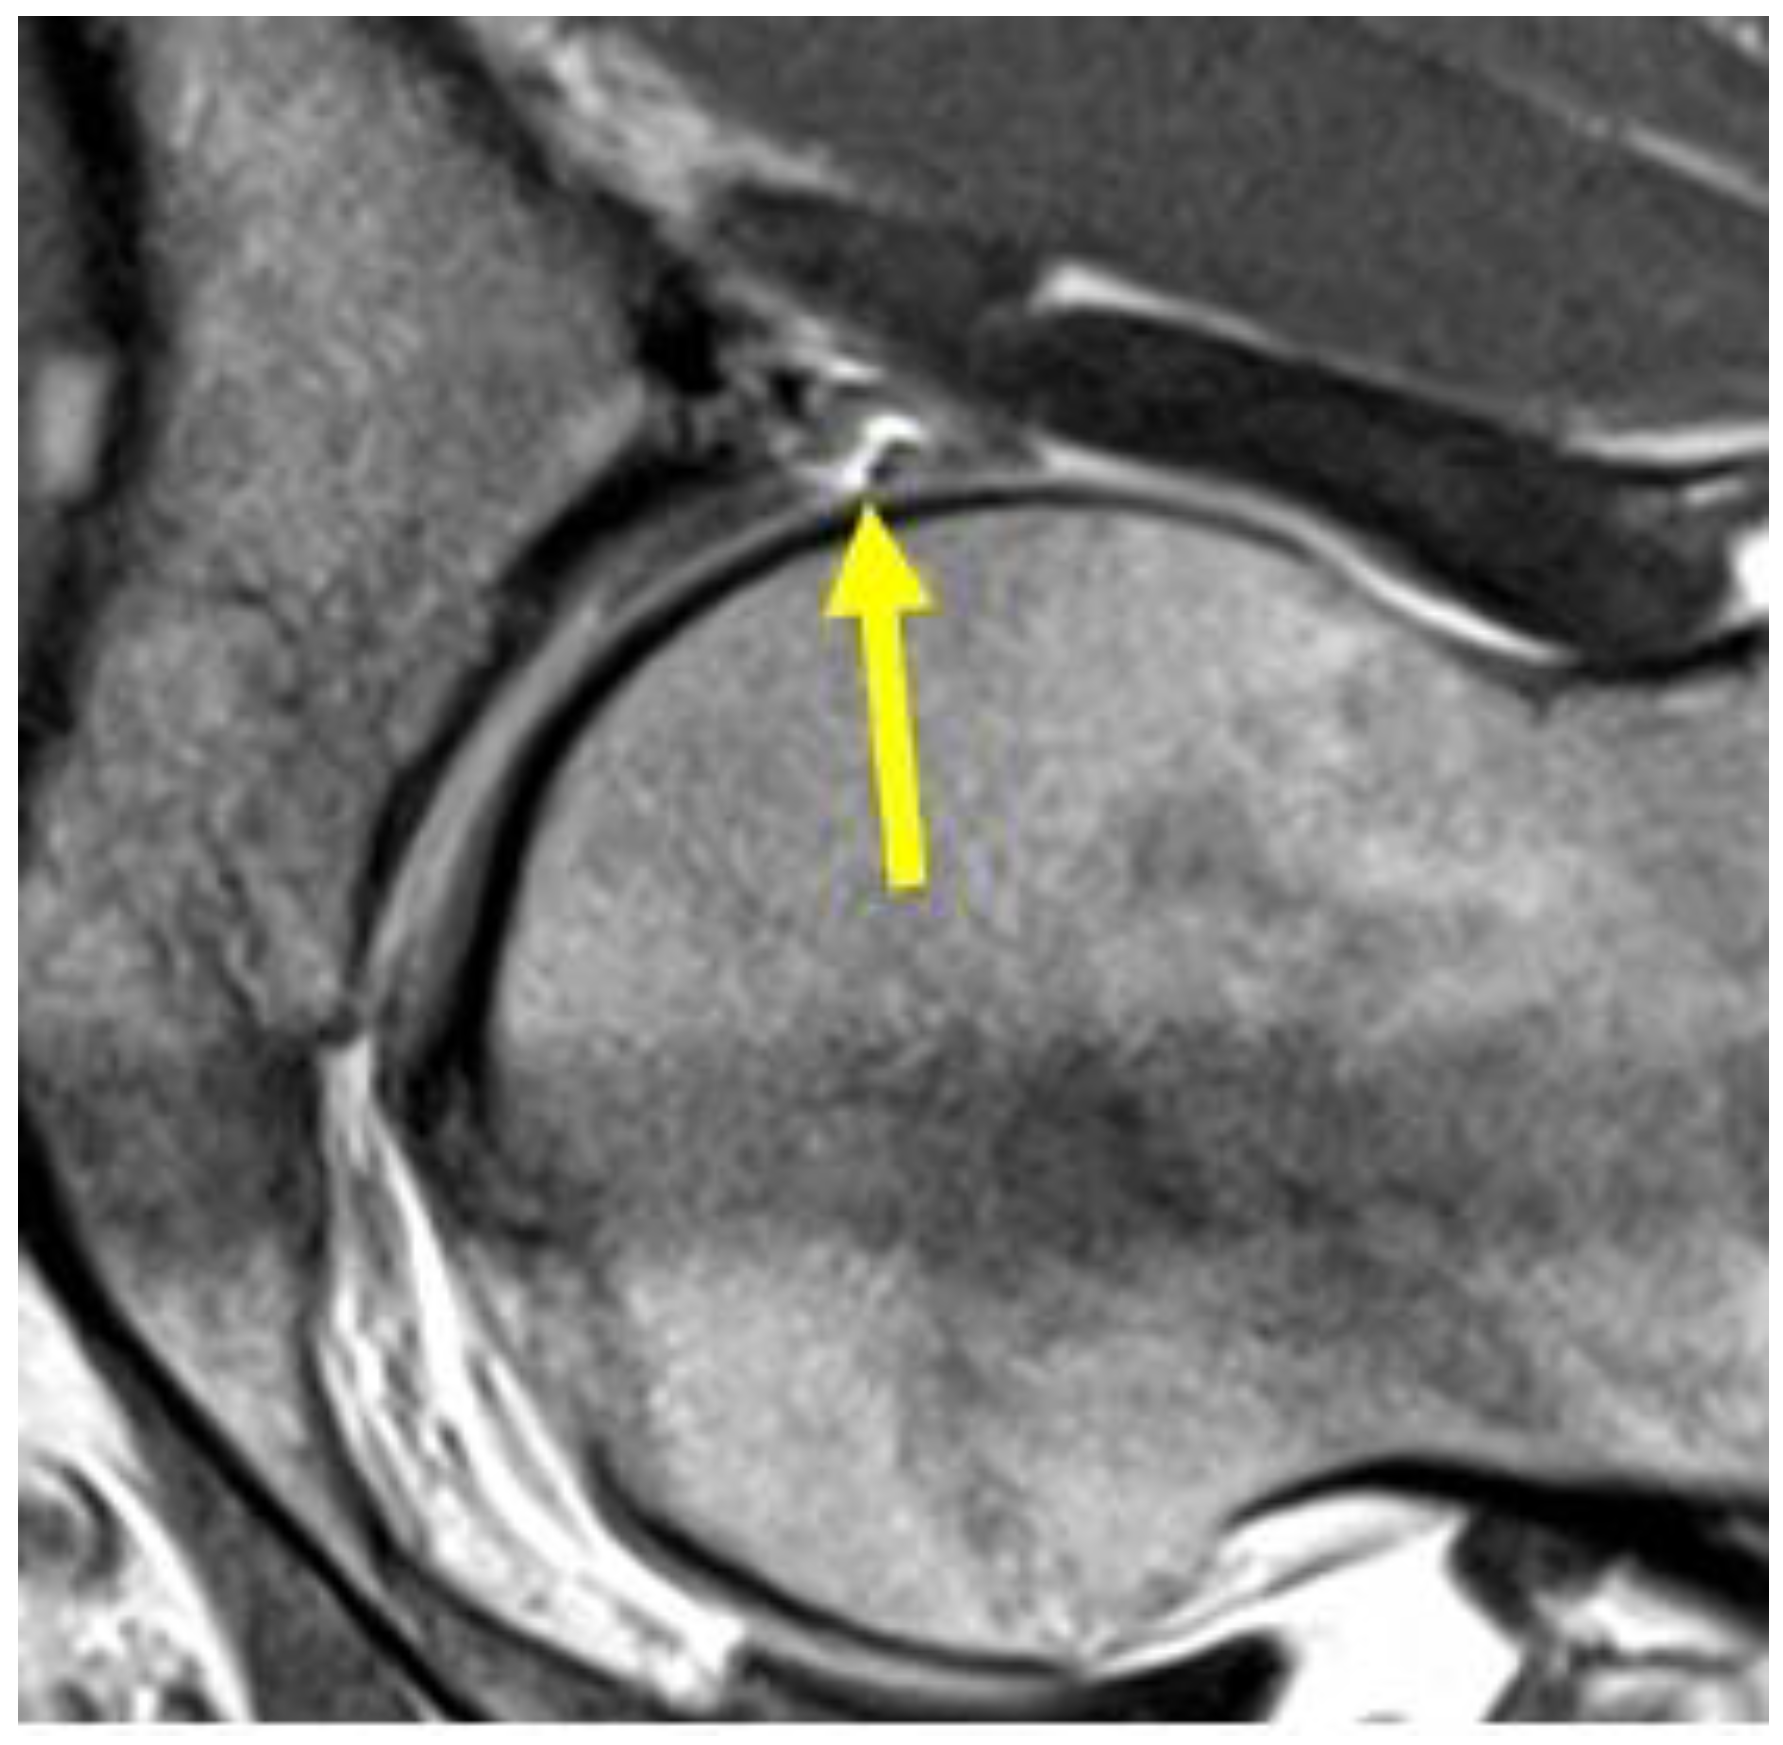

| Acetabular labrum lesion | MRI arthrography: coronal STIR (FOV 30–40 cm); coronal PD or intermediate FS (FOV 16 cm); sagittal or intermediate FS (FOV 16 cm); radiant T1 or T1 FS. | Spreading of the contrast medium into the labral defect. |